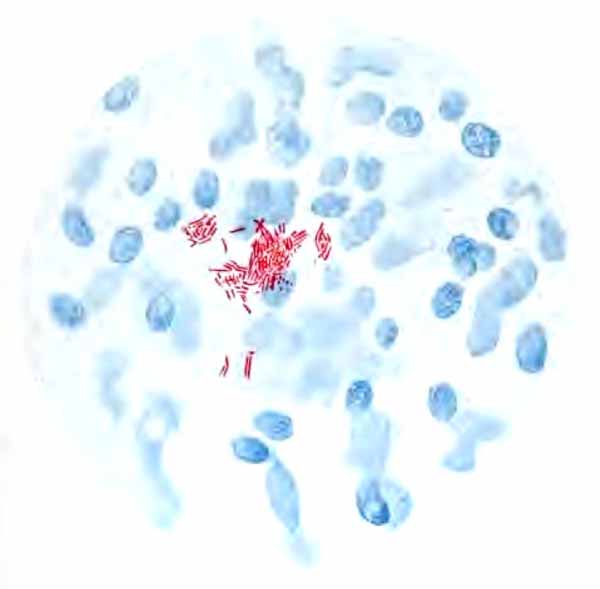

In films stained by Gabbet's method tubercle bacilli, if present, will be seen as slender red rods upon a blue background of mucus and cells (Plate II, Fig. 2). They average 3 to 4 µ in length—about one-half the diameter of a red blood-corpuscle. Beginners must be warned against mistaking the edges of cells, or particles which have retained the red stain, for bacilli. The appearance of the bacilli is almost always typical, and if there seems room for doubt, the structure in question is probably not a tubercle bacillus. They may lie singly or in groups. They are very frequently bent and often have a beaded appearance. It is possible that the larger, beaded bacilli indicate a less active tuberculous process than do the smaller, uniformly stained ones. Sometimes they are present in great numbers—thousands in a field of the one-twelfth objective. Sometimes several cover-glasses must be examined to find a single bacillus. At times they are so few that none are found in stained smears, and special methods are required to detect them. The number may bear some relation to the severity of the disease, but this relation is by no means constant. The mucoid sputum from an incipient case sometimes contains great numbers, while sputum from large tuberculous cavities at times contains very few. Failure to find them is not conclusive, though their absence is much more significant when the sputum is purulent than when it is mucoid.

Sputum showing tubercle bacilli

FIG. 2.—A, Sputum showing tubercle bacilli stained with carbol-fuchsin and Gabbet's methylene-blue solution (obj. one-twelfth oil-immersion); B, sputum of anthracosis, showing particles of coal-dust stained with methylene-blue (obj. one-twelfth oil-immersion) (Boston).